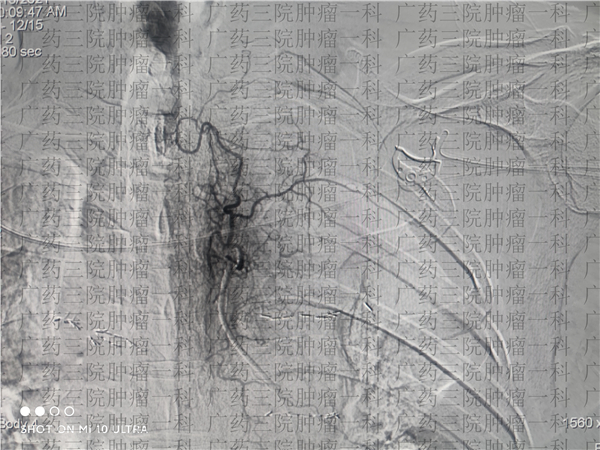

2021年9月13日,刘跃军教授和罗福医生为魏先生进行了双侧支气管动脉的造影+灌注+栓塞手术。这是一种精准微创治疗技术,通过精准定位肿瘤,将药物直接打在肿瘤内部,同时对肿瘤动脉进行栓塞,以期缩小肿瘤大小。